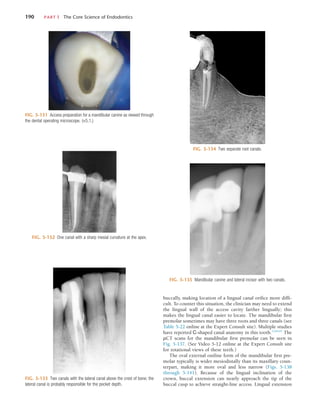

penetration should be assessed for any deviation away from the

long axis of the root in both the mesiodistal and buccolingual

dimensions, and the penetration angle should be realigned if